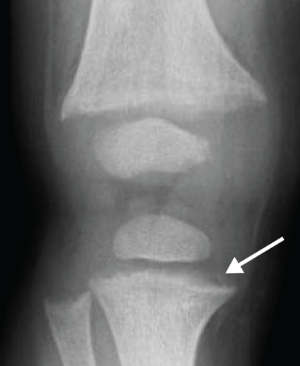

The RSS is a quantitative method that uses radiographs to assess the severity of rickets at the wrists and knees. Originally validated in nutritional rickets, the score is based on the degree of metaphyseal fraying, metaphyseal cupping, and the proportion of the growth plate that is affected. It is a 10-point scale, for which 10 represents the most severe radiographic changes due to rickets and 0 represents the absence of these changes.1

Although the severity and duration of rickets vary considerably between XLH and nutritional rickets, the radiographic features of rickets at the growth plate are similar in the two disorders, which allowed validation of the RSS in XLH. The RSS correlates with serum alkaline phosphatase (ALP) levels, a biochemical marker of rachitic activity, and this scoring system can be used to assess the radiographic response following treatment of nutritional or XLH rickets.

The RSS in XLH has been reported to range from 0 to 4.5; however, despite the smaller RSS range observed in XLH patients, inter- and intra-rater reliability are similar to those reported for nutritional rickets. Patients with XLH who had a baseline RSS ≥1.5 were shown to have more severe hypophosphatemic bone disease, including higher levels of alkaline phosphatase, and greater impairments in clinical outcomes compared with patients who had a baseline RSS <1.5.